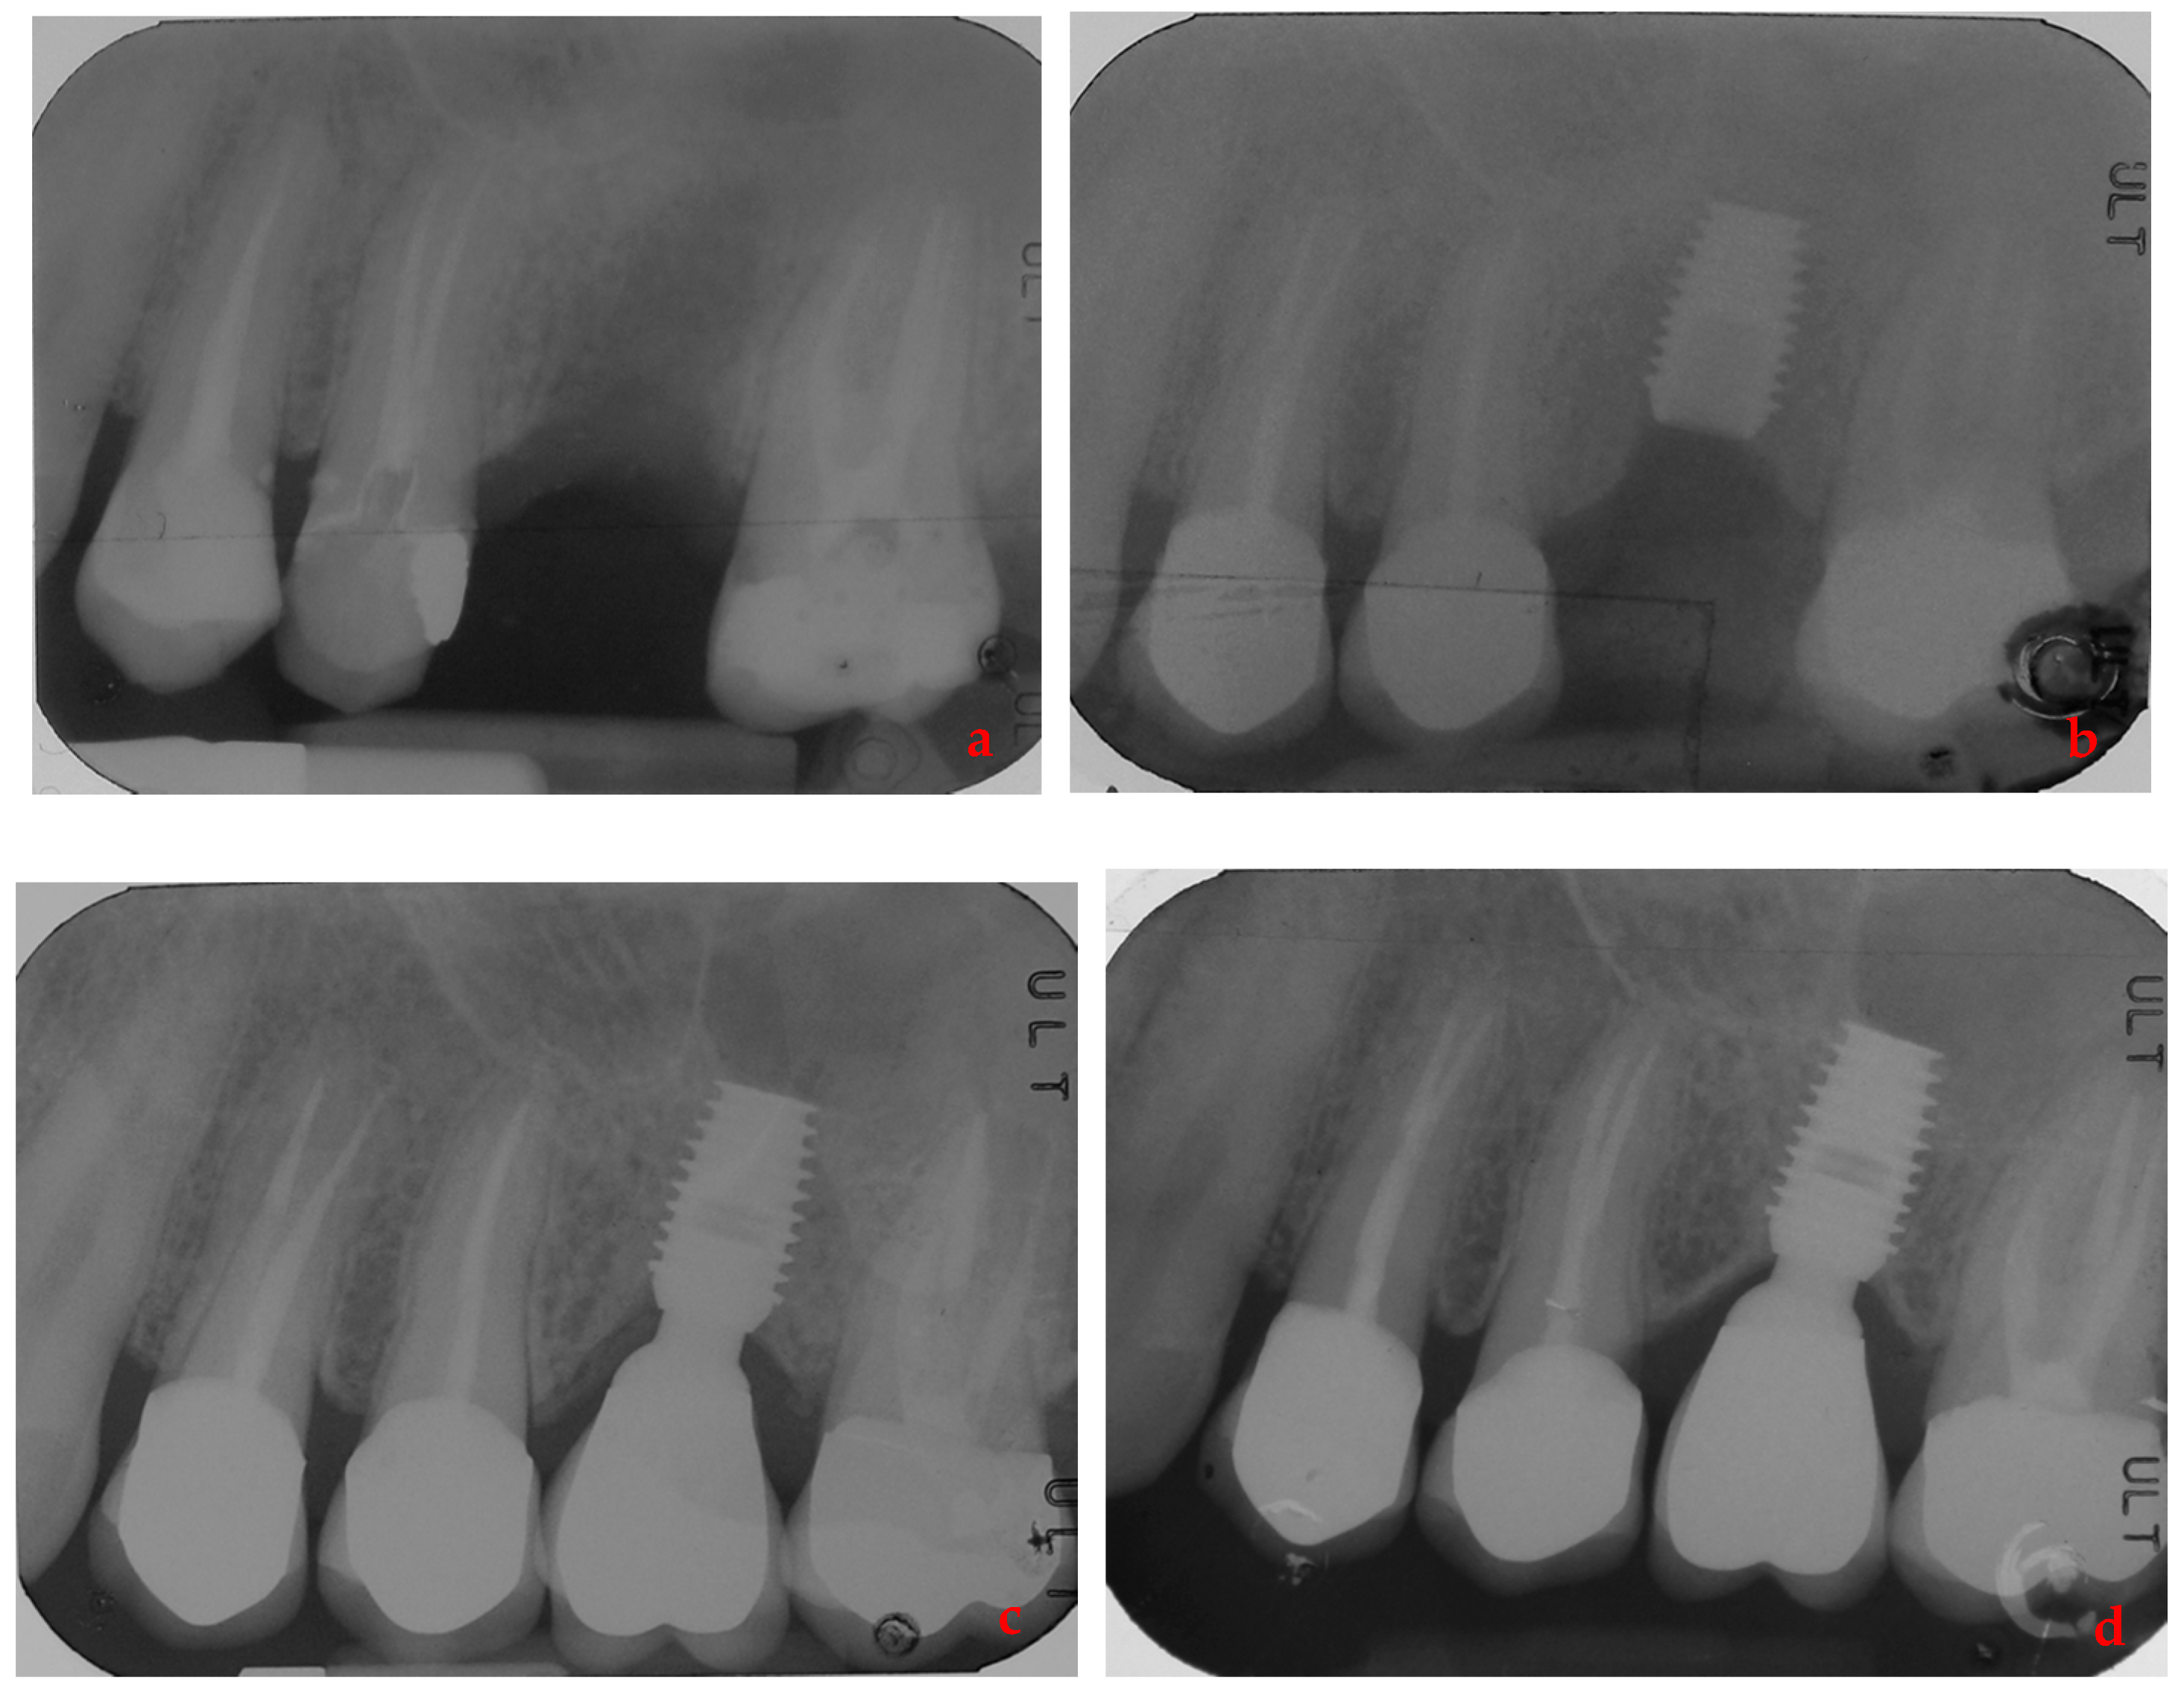

- Lombardo, G.; Signoriello, A.; Simancas-Pallares, M.; Marincola, M.; Nocini, P.F. Survival of Short and Ultra-Short Locking-Taper Implants Supporting Single Crowns in the Posterior Mandible: A 3-Year Retrospective Study. J. Oral Implant. 2020, 46, 396–406. [Google Scholar] [CrossRef] [PubMed]

- Lombardo, G.; Marincola, M.; Signoriello, A.; Corrocher, G.; Nocini, P.F. Single-Crown, Short and Ultra-Short Implants, in Association with Simultaneous Internal Sinus Lift in the Atrophic Posterior Maxilla: A Three-Year Retrospective Study. Materials 2020, 13, 2208. [Google Scholar] [CrossRef] [PubMed]